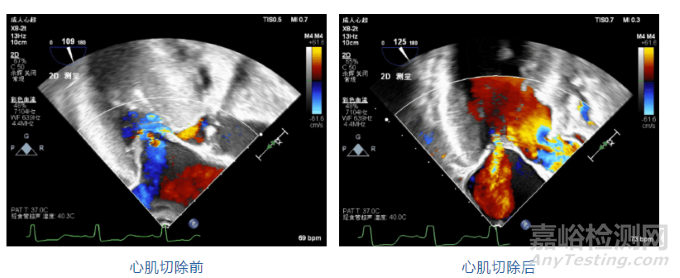

術(shù)中經(jīng)食道超聲:

手術(shù)治療:魏翔教授團(tuán)隊(duì)與馬量主任團(tuán)隊(duì)對患者的術(shù)前準(zhǔn)備、術(shù)中操作及術(shù)后管理進(jìn)行充分討論,制定了詳細(xì)的手術(shù)方案。在患者左側(cè)小切口行經(jīng)心尖室間隔心肌切除,使用微創(chuàng)心肌切除系統(tǒng),對靶心肌切除7次,累計(jì)切除心肌7.8g,操作過程僅耗時(shí)30分鐘左右。

患者情況:患者女性,70歲,半年前出現(xiàn)活動(dòng)后胸悶胸痛,經(jīng)胸超聲心動(dòng)圖顯示:“室間隔增厚,以基底段明顯,并向左室流出道突出;靜息狀態(tài)下左室流出道收縮期峰值流速6.42m/s,峰值壓差165mmHg;激發(fā)狀態(tài)下左室流出道峰值流速8.3m/s,峰值壓差276mmHg;二尖瓣中度關(guān)閉不全,SAM征3級;診斷為肥厚型梗阻性心臟病。